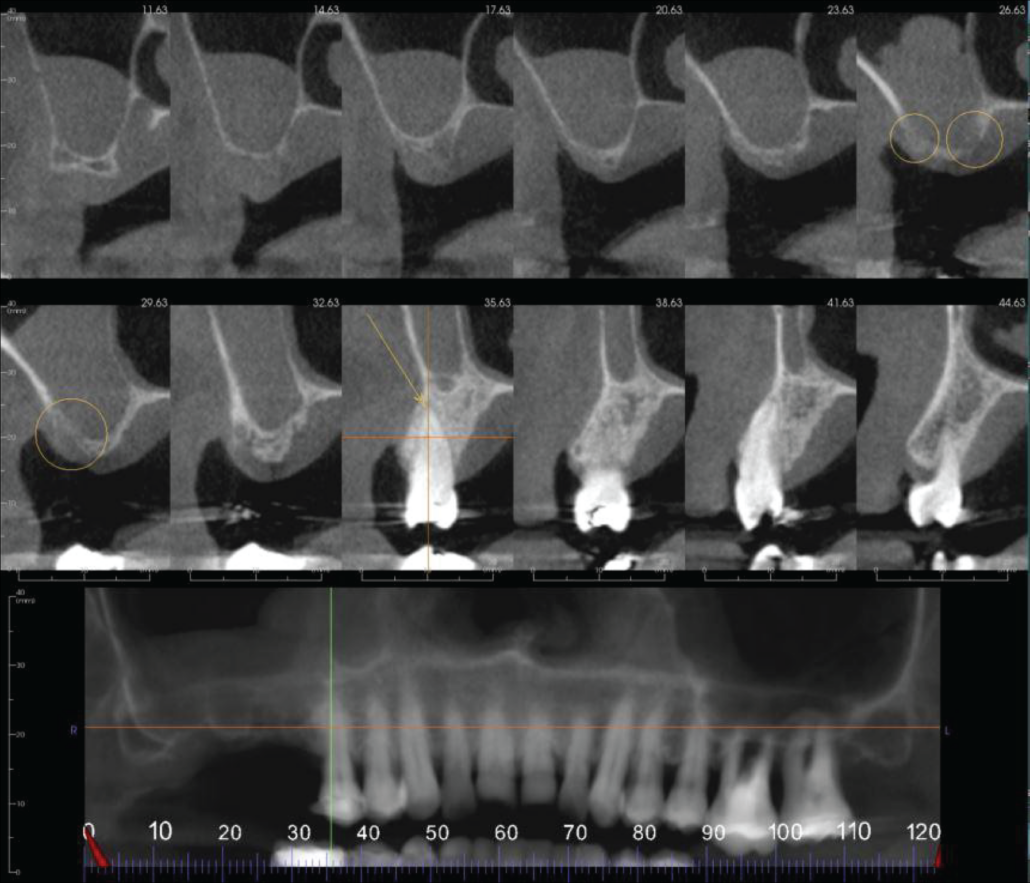

The UR8-6 region has severe loss in vertical alveolar ridge height. The UR5 has widening of the apical periodontal ligament space with evidence of apical pathology. This could be a fibrous scar, an apical granuloma or radicular cyst secondary to chronic apical periodontitis.

The right maxillary sinus has severe mucosal thickening with erosion of the sinus cortical floor and part of the alveolar ridge in the UR6 region. ENT referral is suggested to rule out malignancy.

Cropped panoramic and cross sections of the UR8-4 region. The UR8-6 has severe loss in vertical alveolar ridge height. The UR6 region has erosion of the maxillary sinus cortical floor and alveolar ridge (circled). The UR5 has widening of the apical periodontal ligament space (arrow).